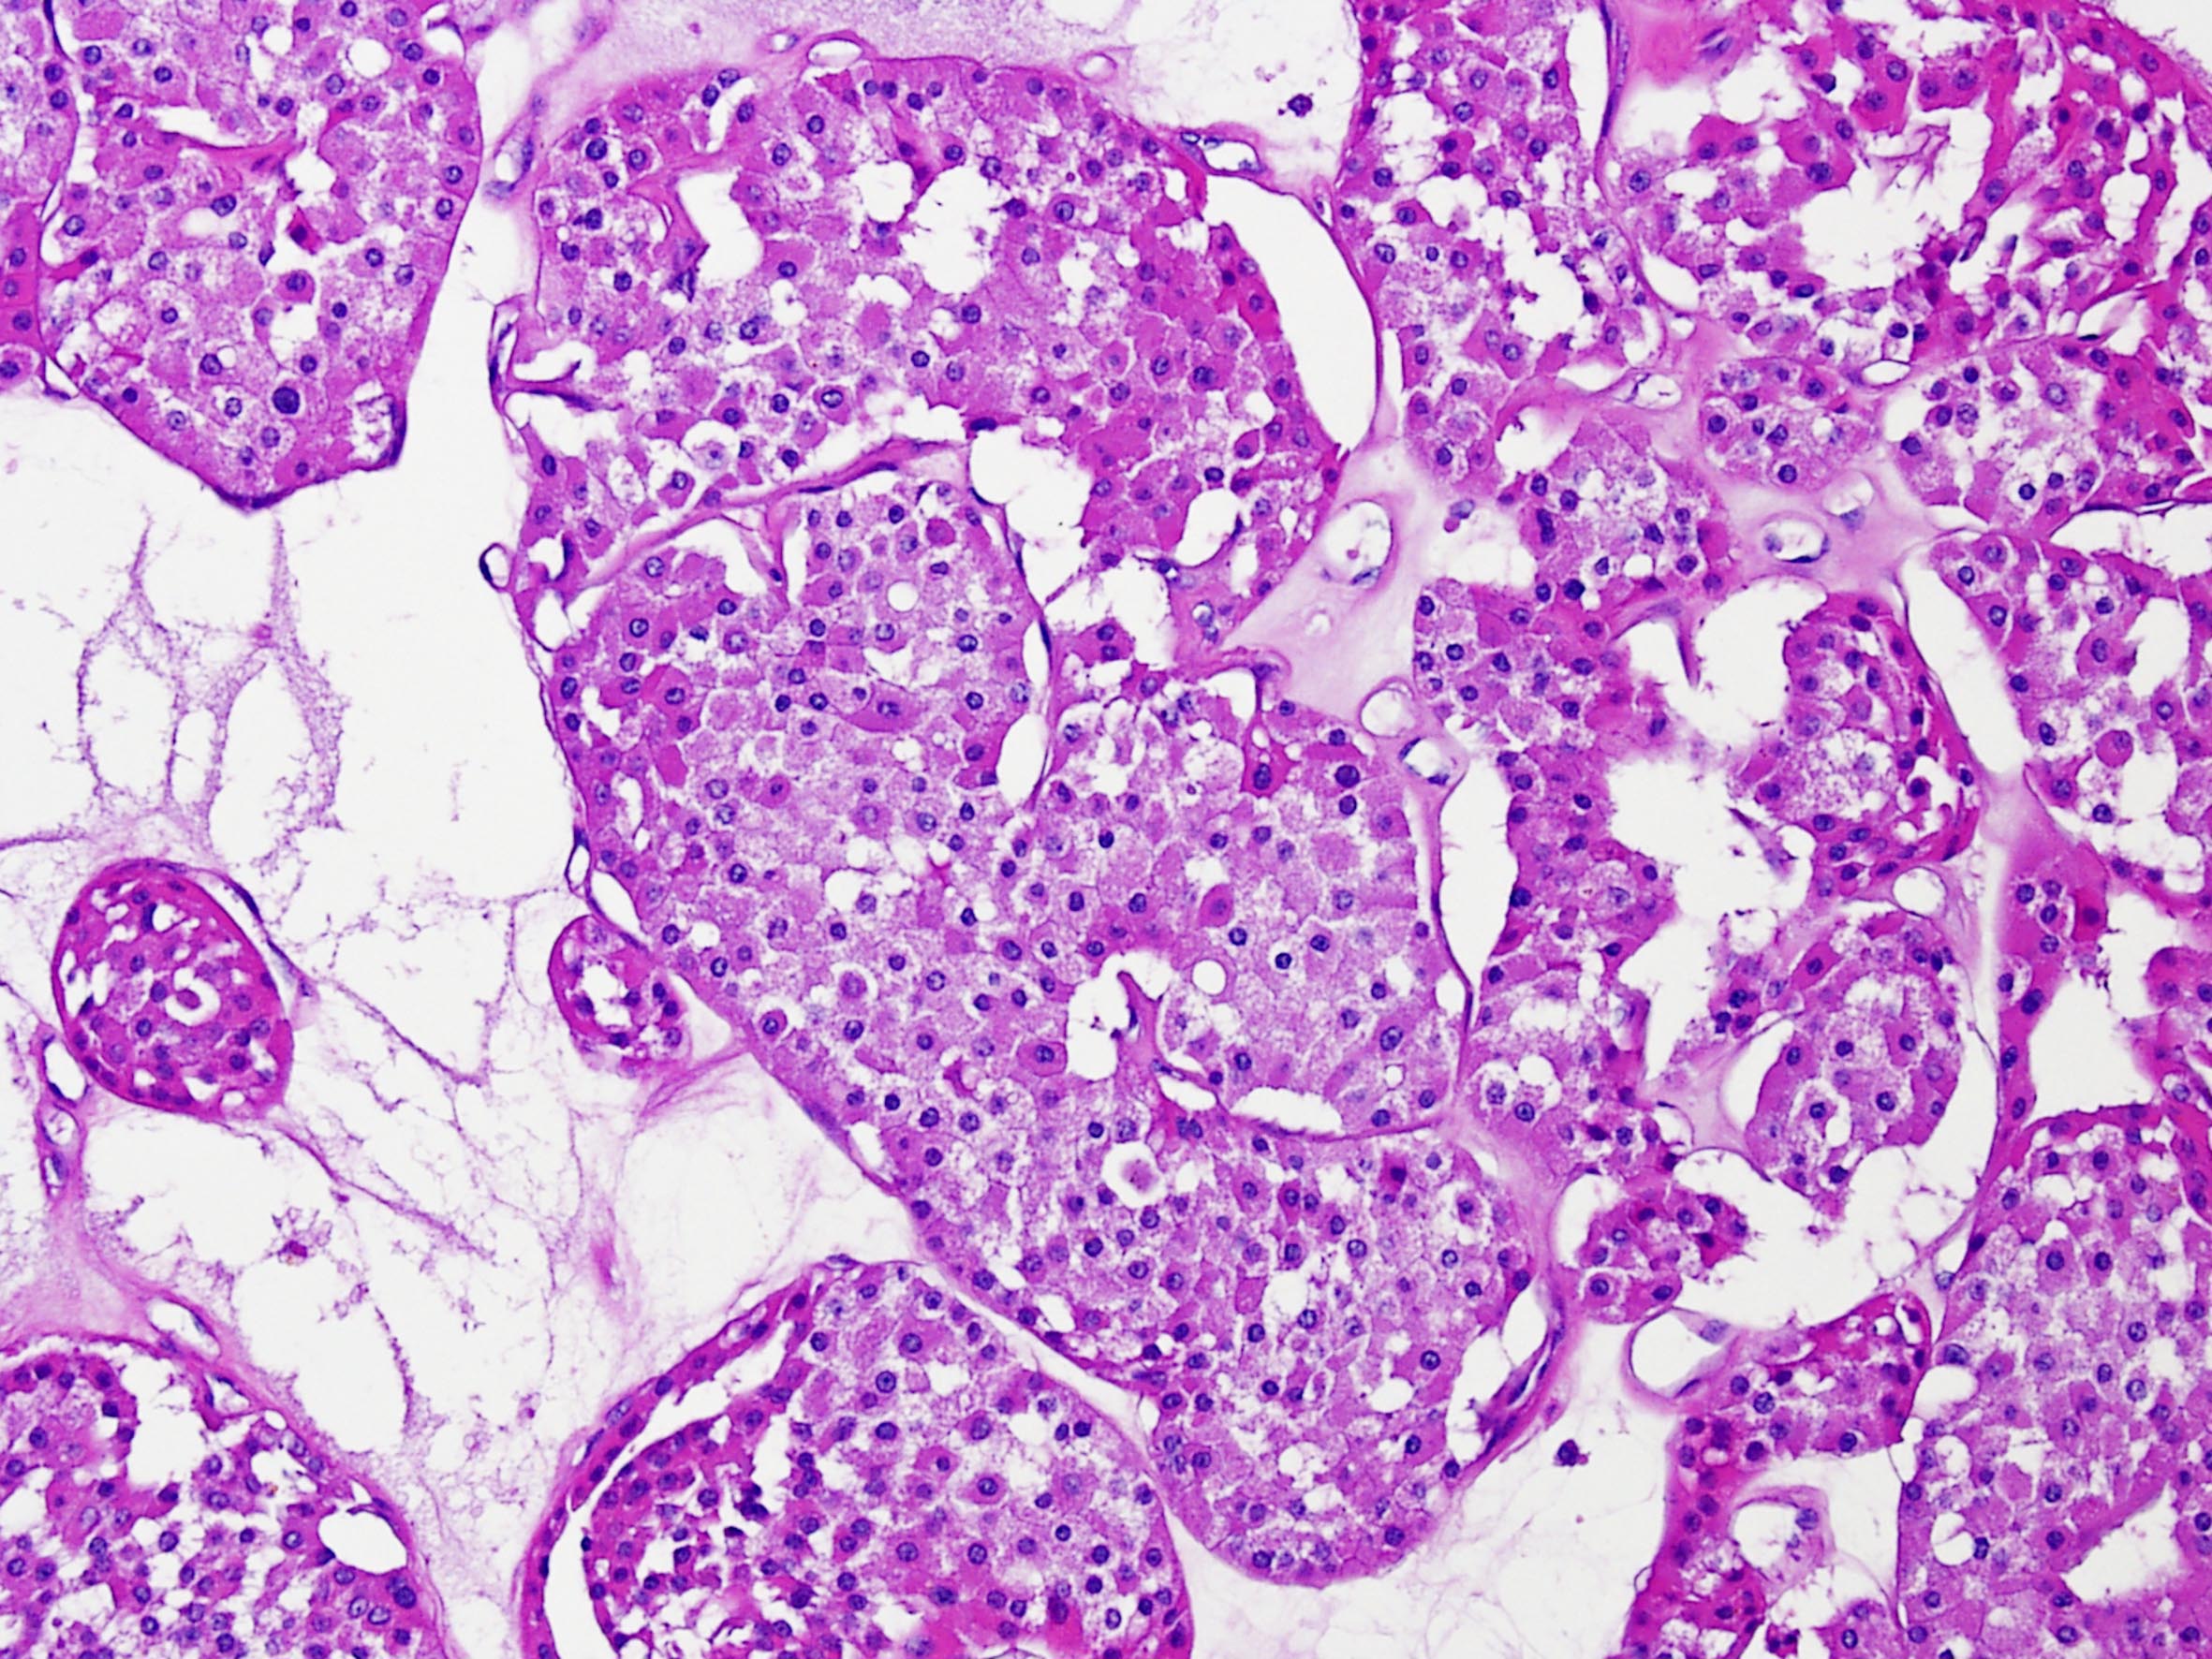

Renal tumor grading

Case ID: 290

WHO/ISUP grade 1

WHO/ISUP grade 2

WHO/ISUP grade 3

WHO/ISUP grade 4